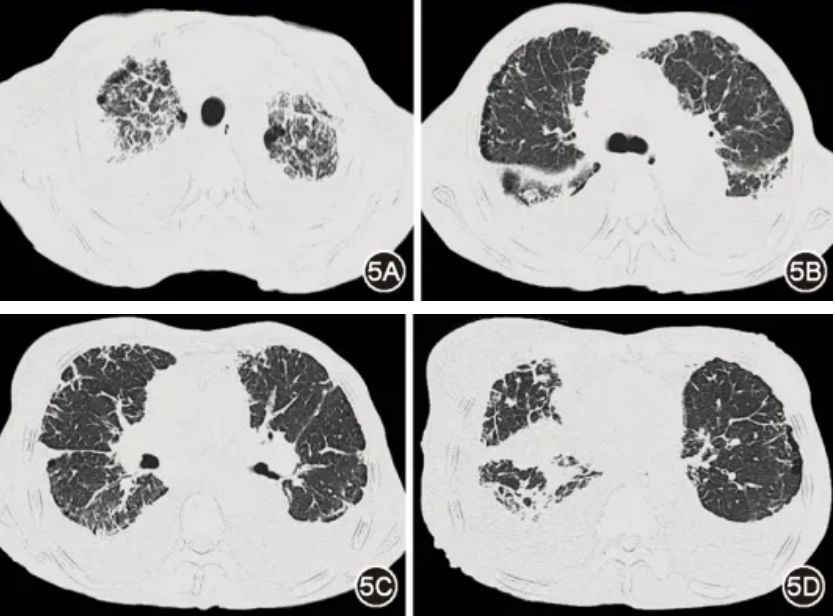

图5 治疗后(2025年10月23日)胸部CT:双肺间质病变、胸腔积液较治疗前轻度加重

后续患者于血液科治疗,目前已完成8程Dara-VenD治疗:达雷妥尤单抗1 800 mg/次、1次/周;维奈克拉200 mg/次(因白细胞低减量)、1次/d;地塞米松20 mg/次、1次/周。气短好转,右乳及下肢水肿部分减轻,可耐受家务活动,监测指氧饱和度94%左右。治疗9个月后复查血游离轻链κ下降至9.9 mg/L,血液学完全缓解,心脏病情稳定,CT示双肺间质病变、胸腔积液轻度加重(图5),考虑和已沉积的淀粉样物质清除困难有关,但病情进展速度减缓。